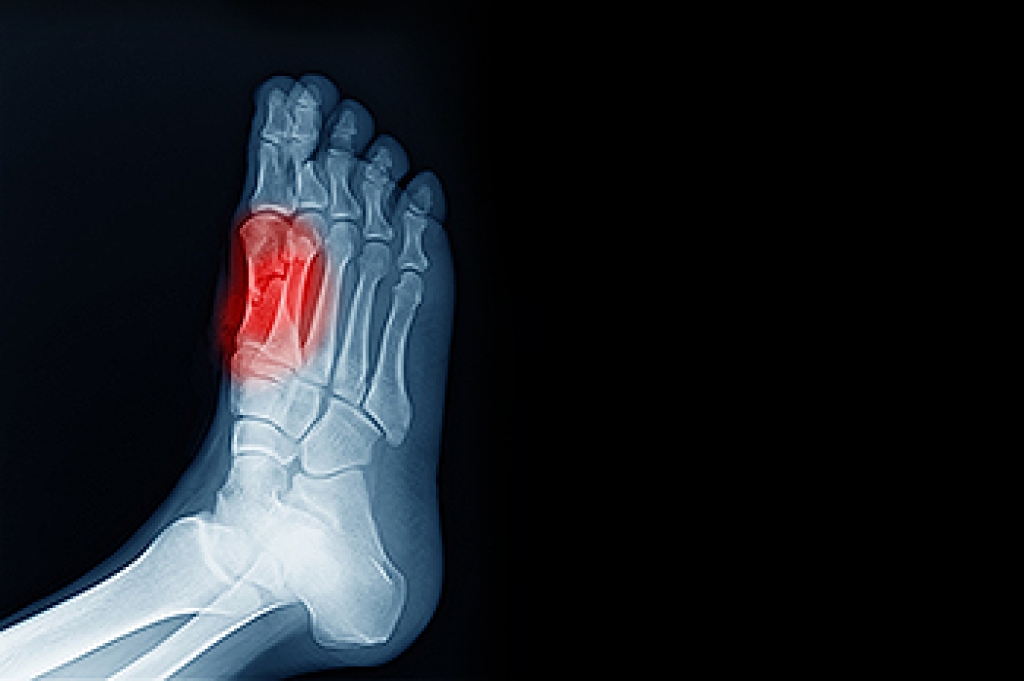

Arthritis is a joint disorder that involves the inflammation of different joints in your body, such as those in your feet. Arthritis is often caused by a degenerative joint disease and causes mild to severe pain in all affected areas. In addition to this, swelling and stiffness in the affected joints can also be a common symptom of arthritis.